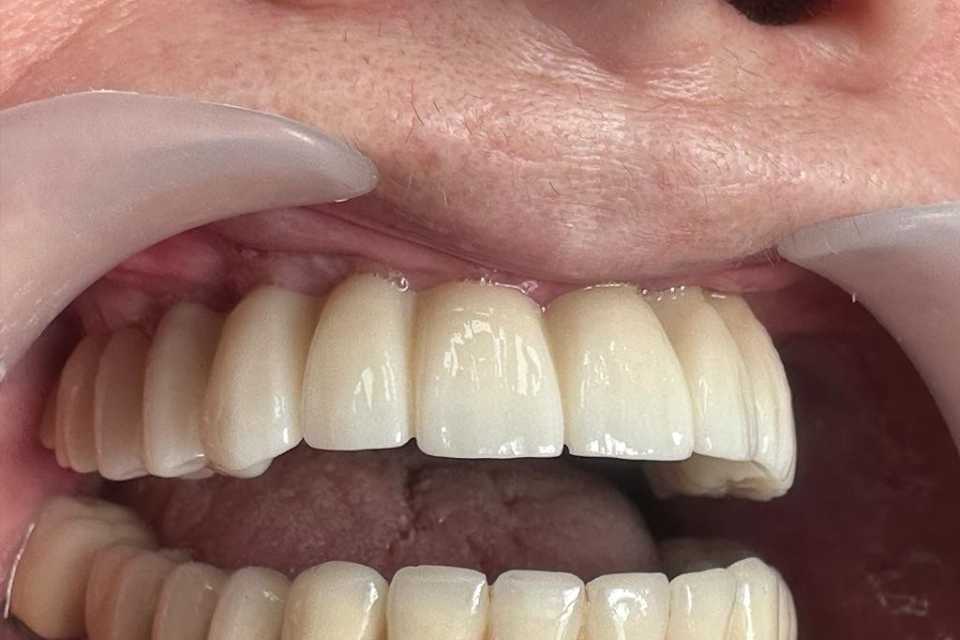

Pentru a răspunde nevoilor sale, s-a optat pentru utilizarea unor implanturi orale speciale: 4 implanturi zigomatice, 2 implanturi pterigoide și 1 implant standard. Această abordare a permis reabilitarea completă a arcadei dentare superioare printr-o lucrare protetică fixă, înșurubabilă, realizată din ceramică pe suport de zirconiu.